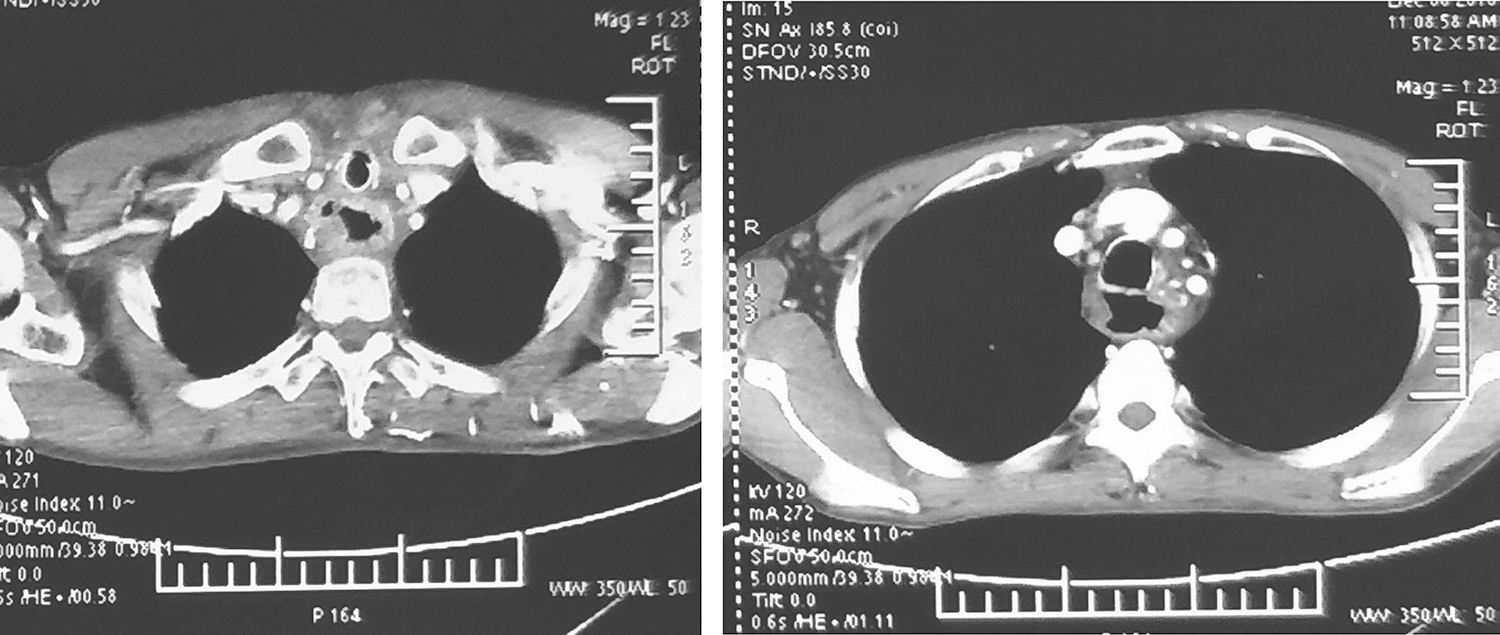

术后每3个月复查,每半年行颈胸强化CT检查(图4)。现已随访1年10个月,健在,无复发及转移。

图4颈胸部增强CT示无肿瘤复发或转移